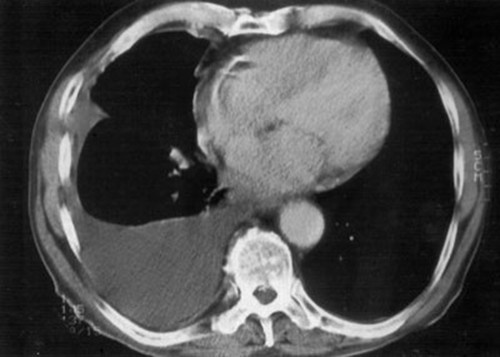

最后CT结果果然出现了阳性结果:右侧胸腔积液!

也就是说导致患者右侧肋部疼痛、间断咳嗽的根本原因是胸腔积液!

我拿着这位年仅40岁的男性患者的胸部CT片子,认真的告诉他:“这恐怕并不是输液那么简单的事情了,你现在需要住院。住院的目的一是明确胸腔积液的原因和性质,二是要做胸腔穿刺等支持治疗。”

因为当时胸部CT的检查结果提示大量胸腔积液,而最可怕的并不是胸痛气短的症状,而是患者为什么会出现如此大量的胸腔积液?